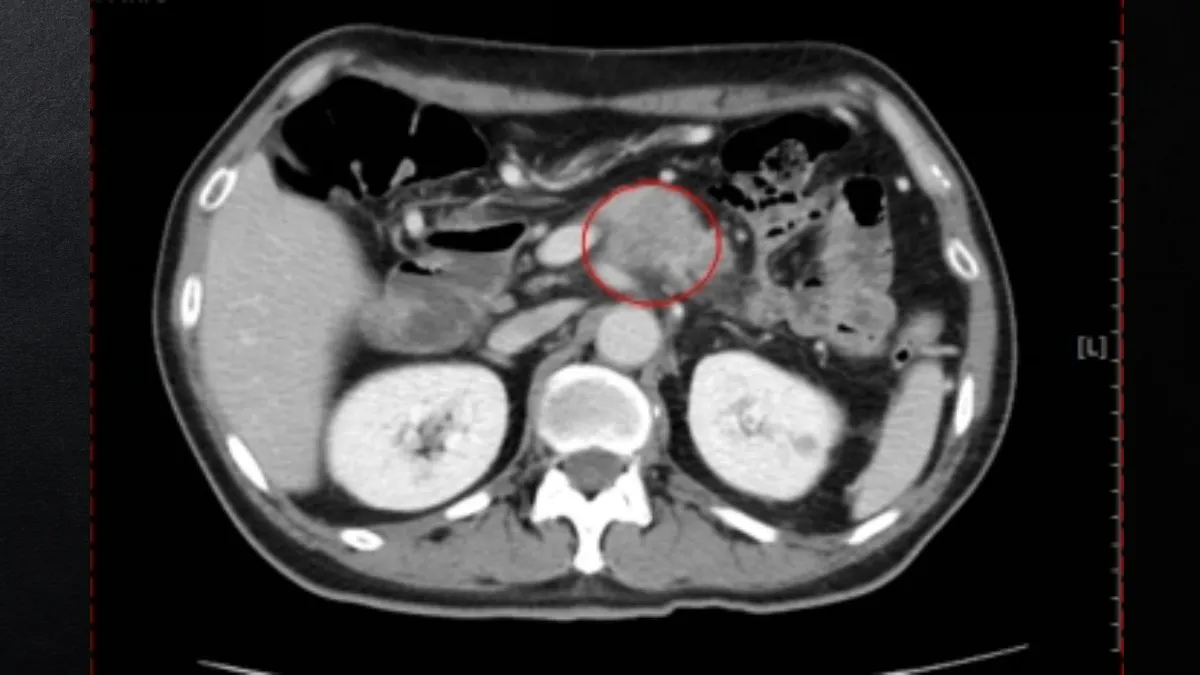

林幸宜表示,該名52歲患者因持續腹部悶痛、飽脹感且進食量減少而就診。抽血發現腫瘤標記CA19-9高達718.92u/ml(正常值小於37u/ml),由於胰臟腫瘤位置較深,常受腸胃道氣體阻擋導致腹部超音波產生盲點,最後經由腹部電腦斷層檢查,確診為3.5公分的胰臟癌。